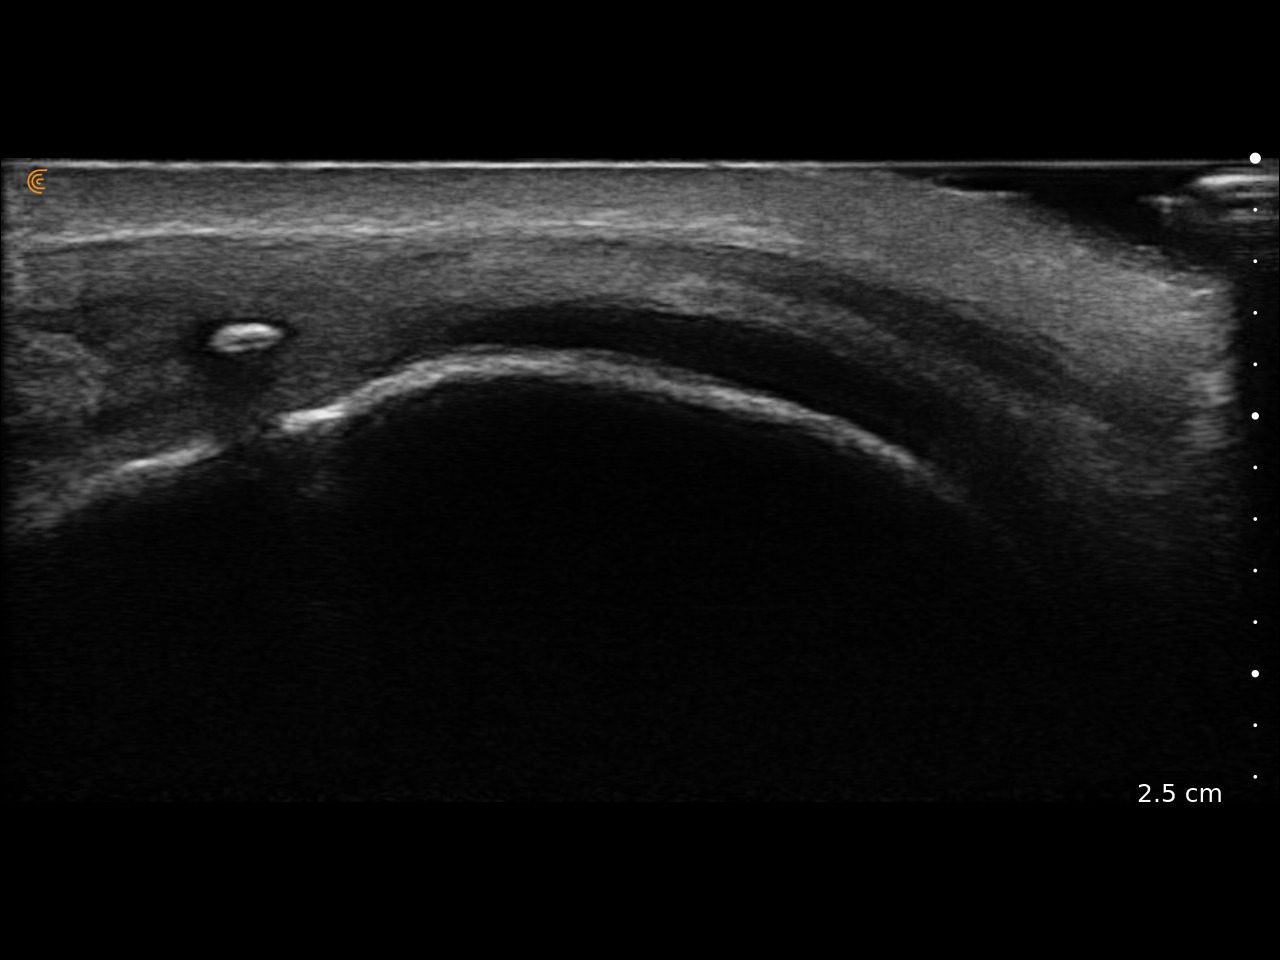

Visualize targets in real time to deliver PRP or cortisone—even in complex joints. Instantly diagnose sprains, tears, and effusions, and make confident decisions about surgical intervention

Use real-time imaging to assess injuries, monitor recovery, and tailor treatment plans—delivering better outcomes for every patient.

Assess synovitis, enthesitis, and monitor treatment efficacy with high-resolution ultrasound, enabling precise, real-time joint and soft tissue evaluation, accurate needle guidance, and improved confidence in clinical decision-making.